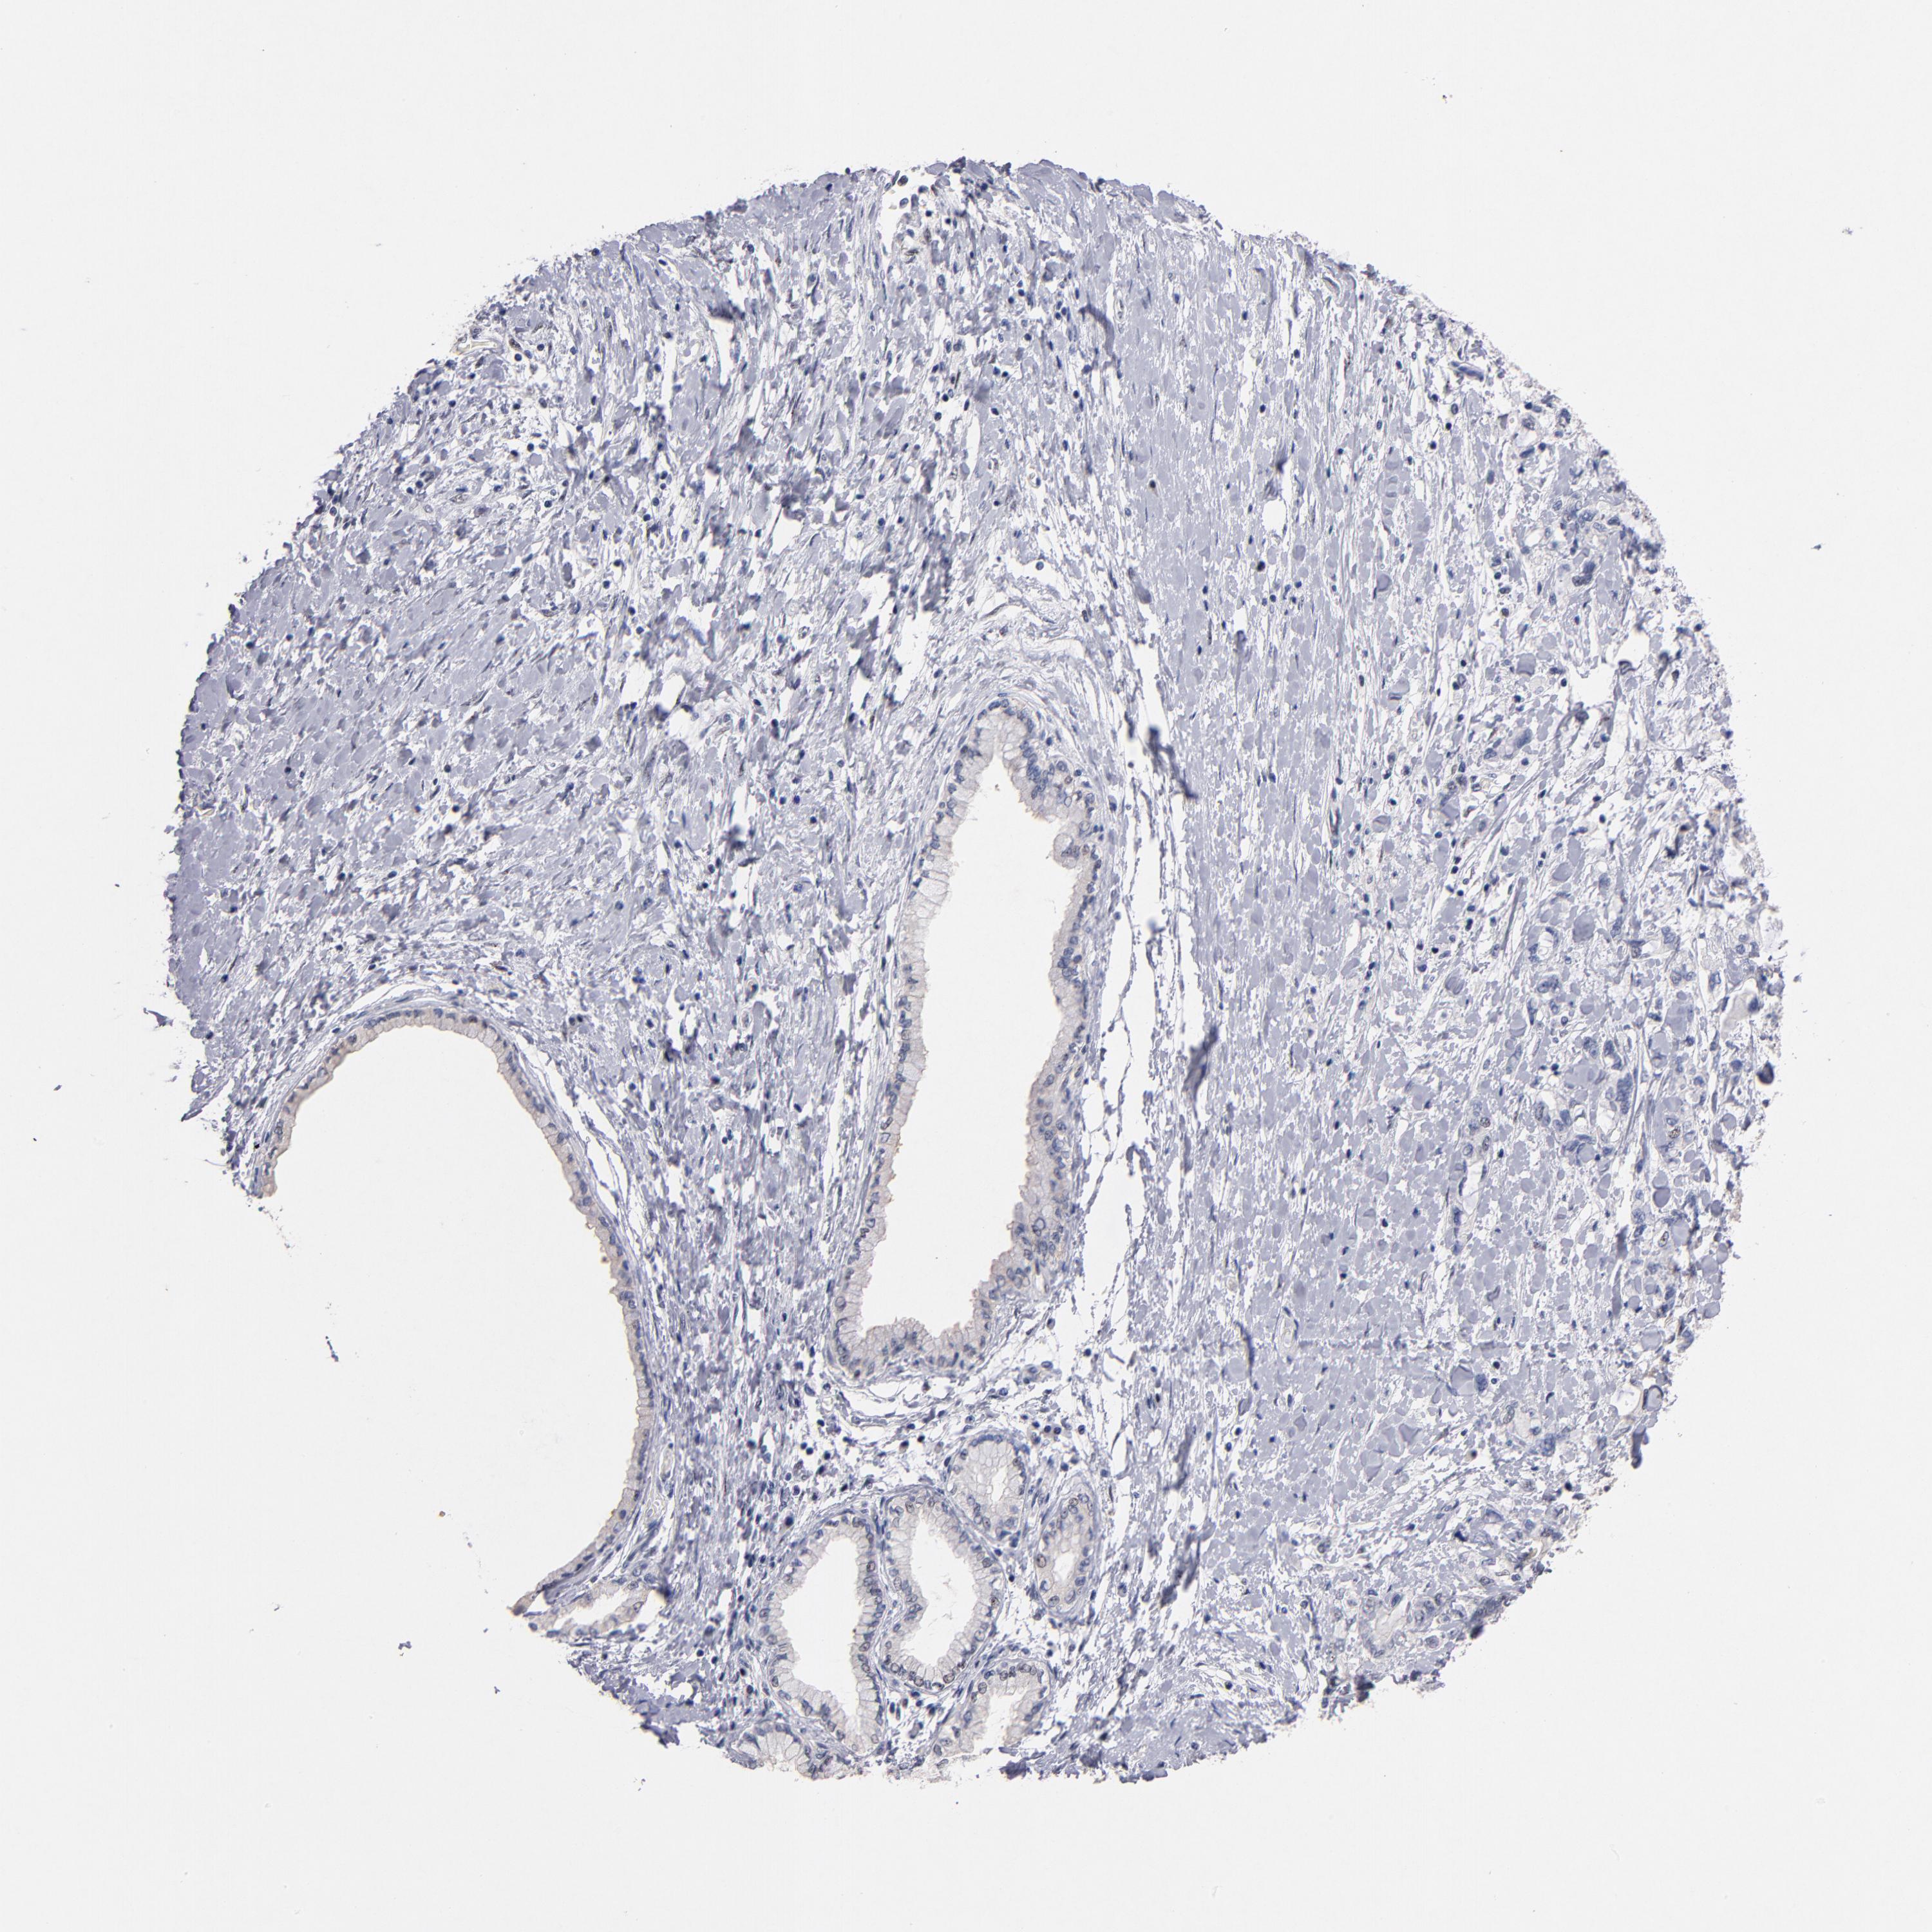

PANCREATIC CANCER - Protein expressioni

A mouse-over function shows sample information and annotation data. Click on an image to view it in a full screen mode. Samples can be filtered based on level of antibody staining by selecting one or several of the following categories: high, medium, low and not detected. The assay and annotation is described here.

Note that samples used for immunohistochemistry by the Human Protein Atlas do not correspond to samples in the TCGA dataset.

Antibody stainingi

Antibody staining in the annotated cell types in the current human tissue is reported as not detected, low, medium, or high, based on conventional immunohistochemistry profiling in selected tissues. This score is based on the combination of the staining intensity and fraction of stained cells.

Each image is clickable and will lead to virtual microscopy that enables deeper exploration of all samples and also displays staining intensity scores, fraction scores and subcellular localization as well as patient and tissue information for each sample.

Antibody HPA002640

Antibody CAB019291

Antibody CAB080384

Adenocarcinoma, NOS

Adenocarcinoma, metastatic, NOS